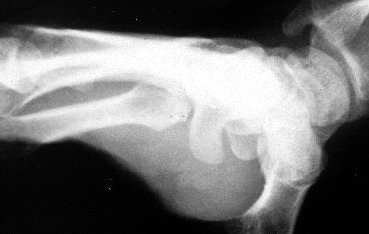

"Cup" Hamate hook Xray view